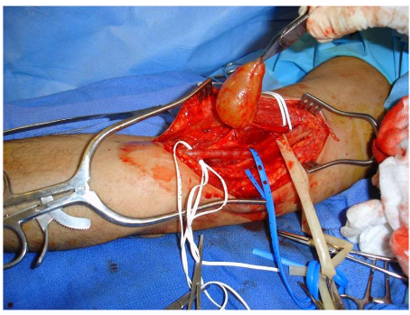

This is an example of a schwannoma, a common benign soft-tissue mass, located in the patient's arm.

This is an intraoperative photo of a schwannoma, a common benign soft-tissue tumor.